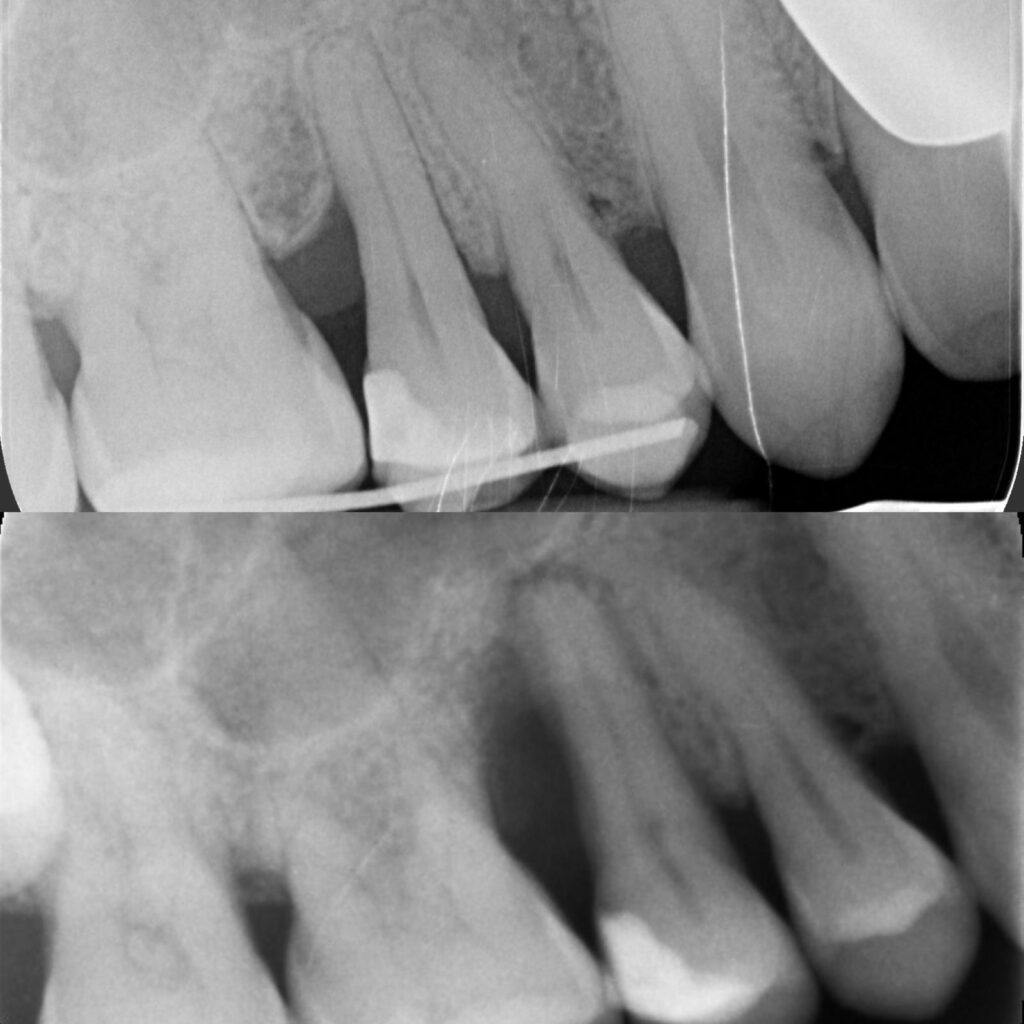

Periodoncia para la clínica de Odontología general. Ventajas, herramienas y gestión.